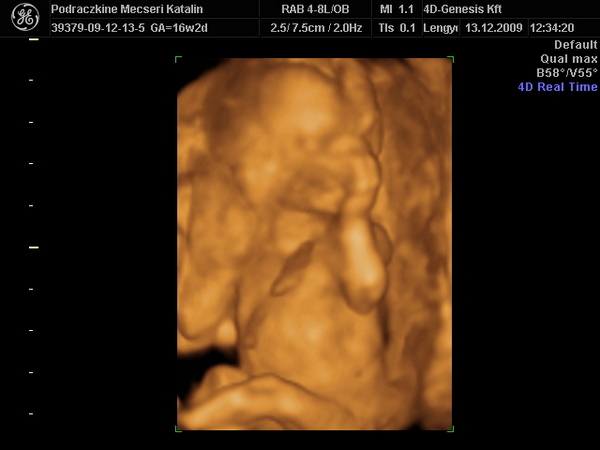

Újabb pasi érkezik Kolos. :D

16 hetesen ilyen. :wink: